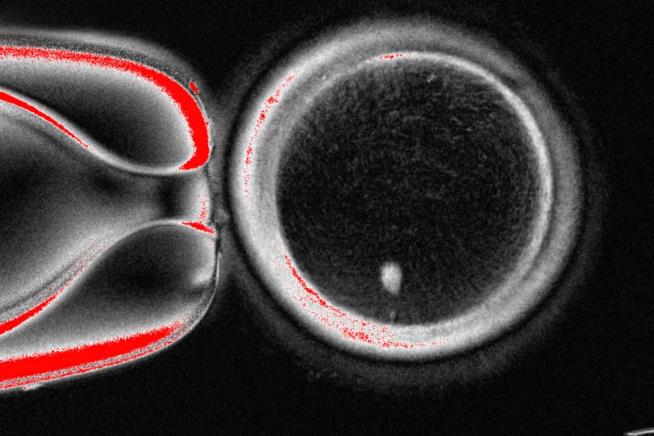

This undated image provided by the Mitalipov Laboratory at Oregon Health & Science University shows a a microscope image of a human egg that contains a nucleus taken from a skin cell. (Mitalipov Laboratory via AP)   (Associated Press)

The OHSU team removed the nucleus from a human egg cell and replaced it with the nucleus from a human skin cell. But a skin cell contains two sets of chromosomes, and eggs and sperm are supposed to each contain only one set that combine during fertilization. The researchers therefore induced the egg-like cells to discard extra chromosomes, injected donated sperm and jumpstarted post-fertilization development.

About 9% lasted for six days in lab dishes, reaching the blastocyst stage of early embryo development, before the experiment was stopped.